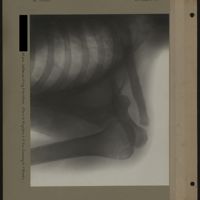

0083 - Page 79 - [Radiographie du coude et de l'avant-bras]0083 - Page 79 - [Radiographie du coude et de l'avant-bras]